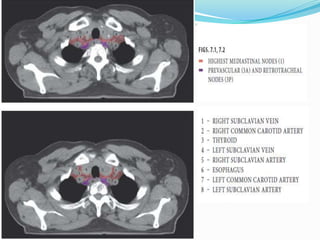

The International Association for the

Study of Lung Cancer Lymph Node Map: A

Radiologic Atlas and Review

 14 LN stations reorganized into 7 zones

The International Associationfor the Study of Lung Cancer Lymph Node Map: A Radiologic Atlas and Review  14 LN stations reorganized into 7 zones  Supraclavicular zone  Upper zone  AP zone  Subcarinal zone  Lower zone  Hilar zone  Peripheral zone